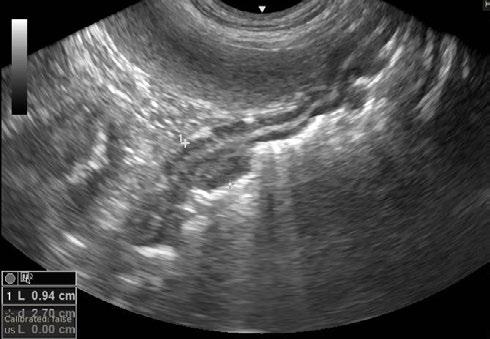

An abdominal ultrasound was performed on Thursday 11th April. The ultrasound showed an area of stomach wall that was thickened up to 2cm in places, with hyperechoic tissue causing loss of stomach wall layering in the region of the thickening. No other abnormalities were seen on ultrasound. Abdominal radiographs were also taken but did not show anything not visible on ultrasound.

2. Ultrasound images showing loss of layering and profound thickening of a portion (stars) of the gastric wall

The Ultrasound ( Figures 4) shows there are still some areas with thickening but they are much smaller than previously. I have recommended she stay on medication for another 3 months and then we will repeat the ultrasound.